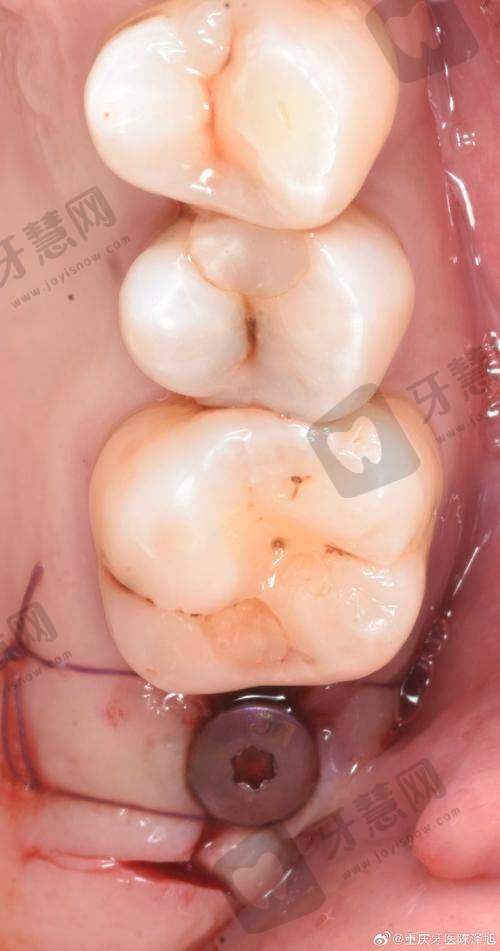

1. 即刻种植修复:该技术可以在拔牙后立即植入种植体,减少患者的就诊次数和等待时间,缩短疗程。同时,能更好地保存牙槽骨的高度和宽度,提高种植的成功几率和美观度。